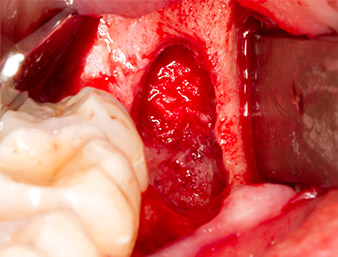

The tissue above the root remnant was not completely ossified and consisted for the most part of granulation tissue modified by inflammation (Fig. 4).

Granulation tissue

Fig. 4: Two Langenbeck retractors and a raspatorium expose the operating area. Granulation tissue of the incompletely healed first osteotomy can be seen.